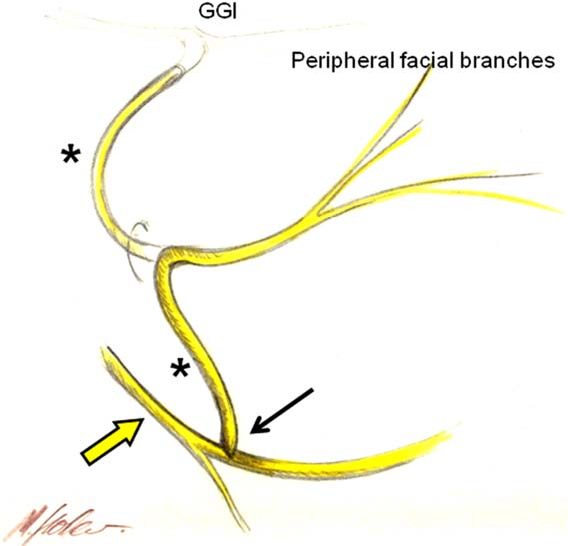

(PDF) Hypoglossal-Facial Nerve Anastomosis in Facial Reanimation: A …

Figure 1 from Comparison of Direct Side-to-End and End-to-End …

Analysis of Preoperative Factors Influencing Hypoglossal-facial ‘Side …

Figure 3 from Hypoglossal-facial-jump-anastomosis without an …

Hypoglossal Facial Anastomosis | Ento Key